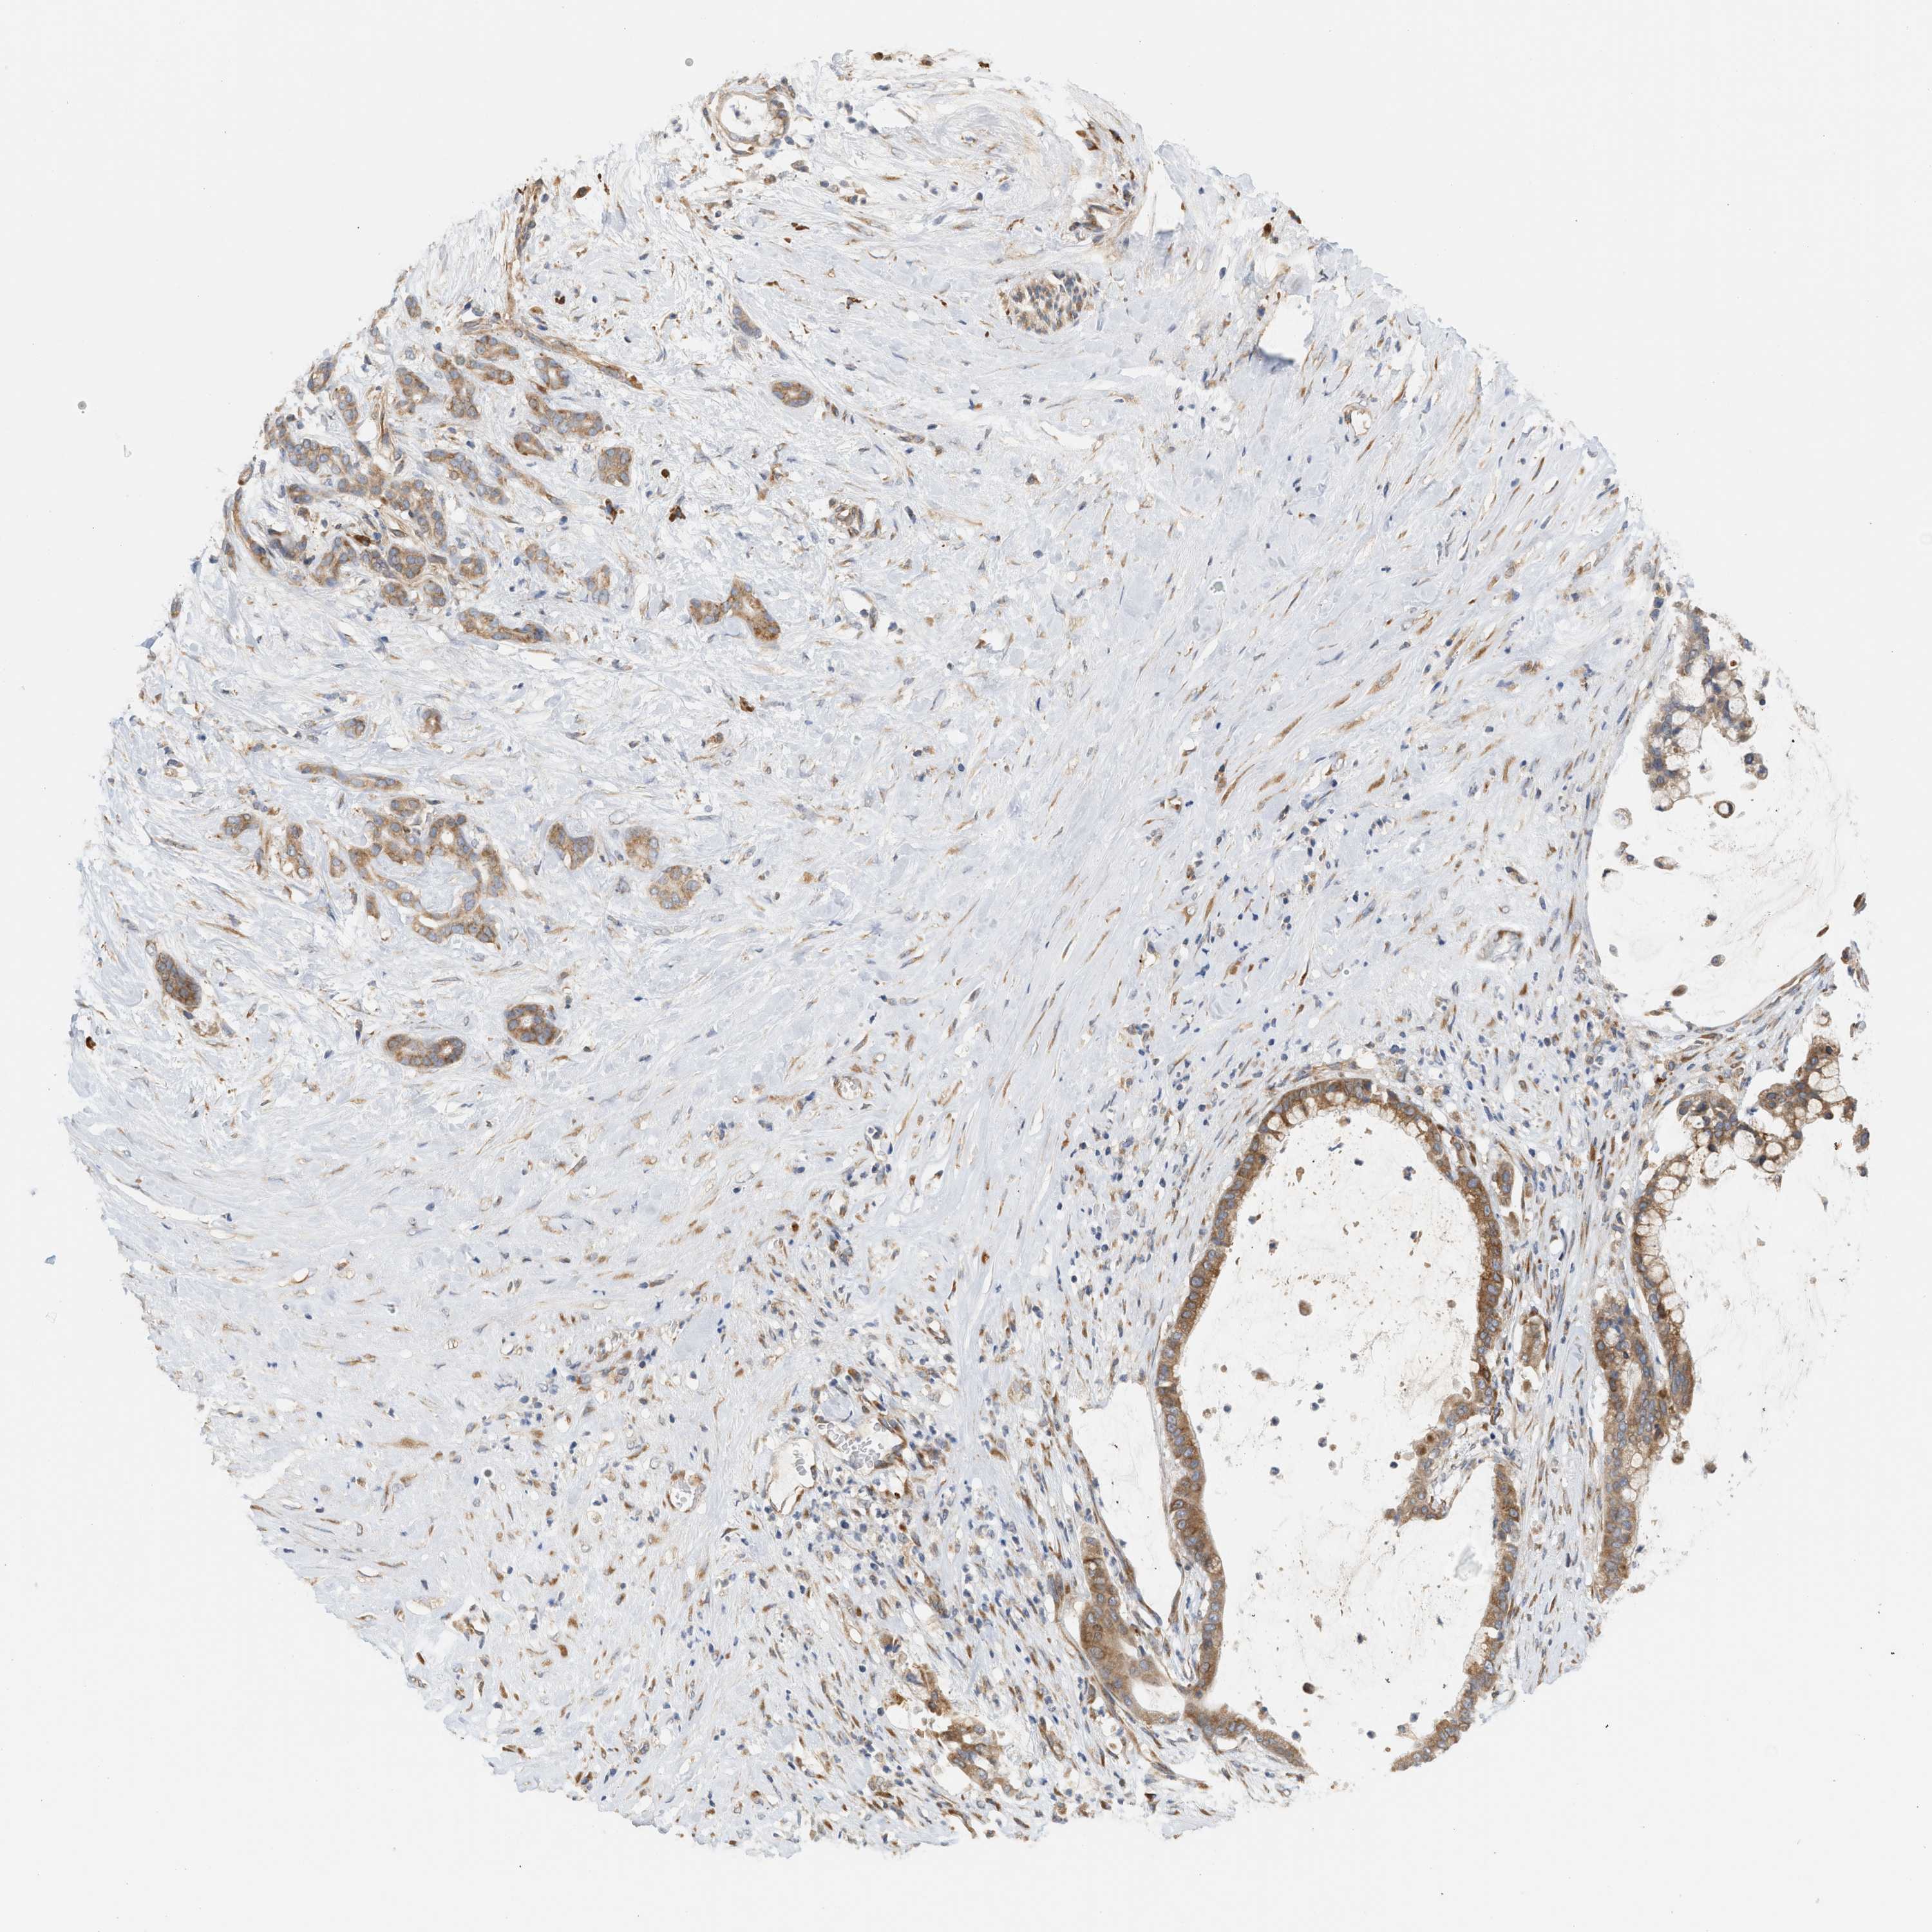

PANCREATIC CANCER - Protein expressioni

A mouse-over function shows sample information and annotation data. Click on an image to view it in a full screen mode. Samples can be filtered based on level of antibody staining by selecting one or several of the following categories: high, medium, low and not detected. The assay and annotation is described here.

Note that samples used for immunohistochemistry by the Human Protein Atlas do not correspond to samples in the TCGA dataset.

Antibody stainingi

Antibody staining in the annotated cell types in the current human tissue is reported as not detected, low, medium, or high, based on conventional immunohistochemistry profiling in selected tissues. This score is based on the combination of the staining intensity and fraction of stained cells.

Each image is clickable and will lead to virtual microscopy that enables deeper exploration of all samples and also displays staining intensity scores, fraction scores and subcellular localization as well as patient and tissue information for each sample.

Antibody HPA016573

Staining

High

Medium

Low

Not detected

Intensity

Strong

Moderate

Weak

Negative

Quantity

>75%

75%-25%

<25%

None

Location

Nuclear

Cytoplasmic/membranous

Cytoplasmic/membranous,nuclear

Adenocarcinoma, NOS